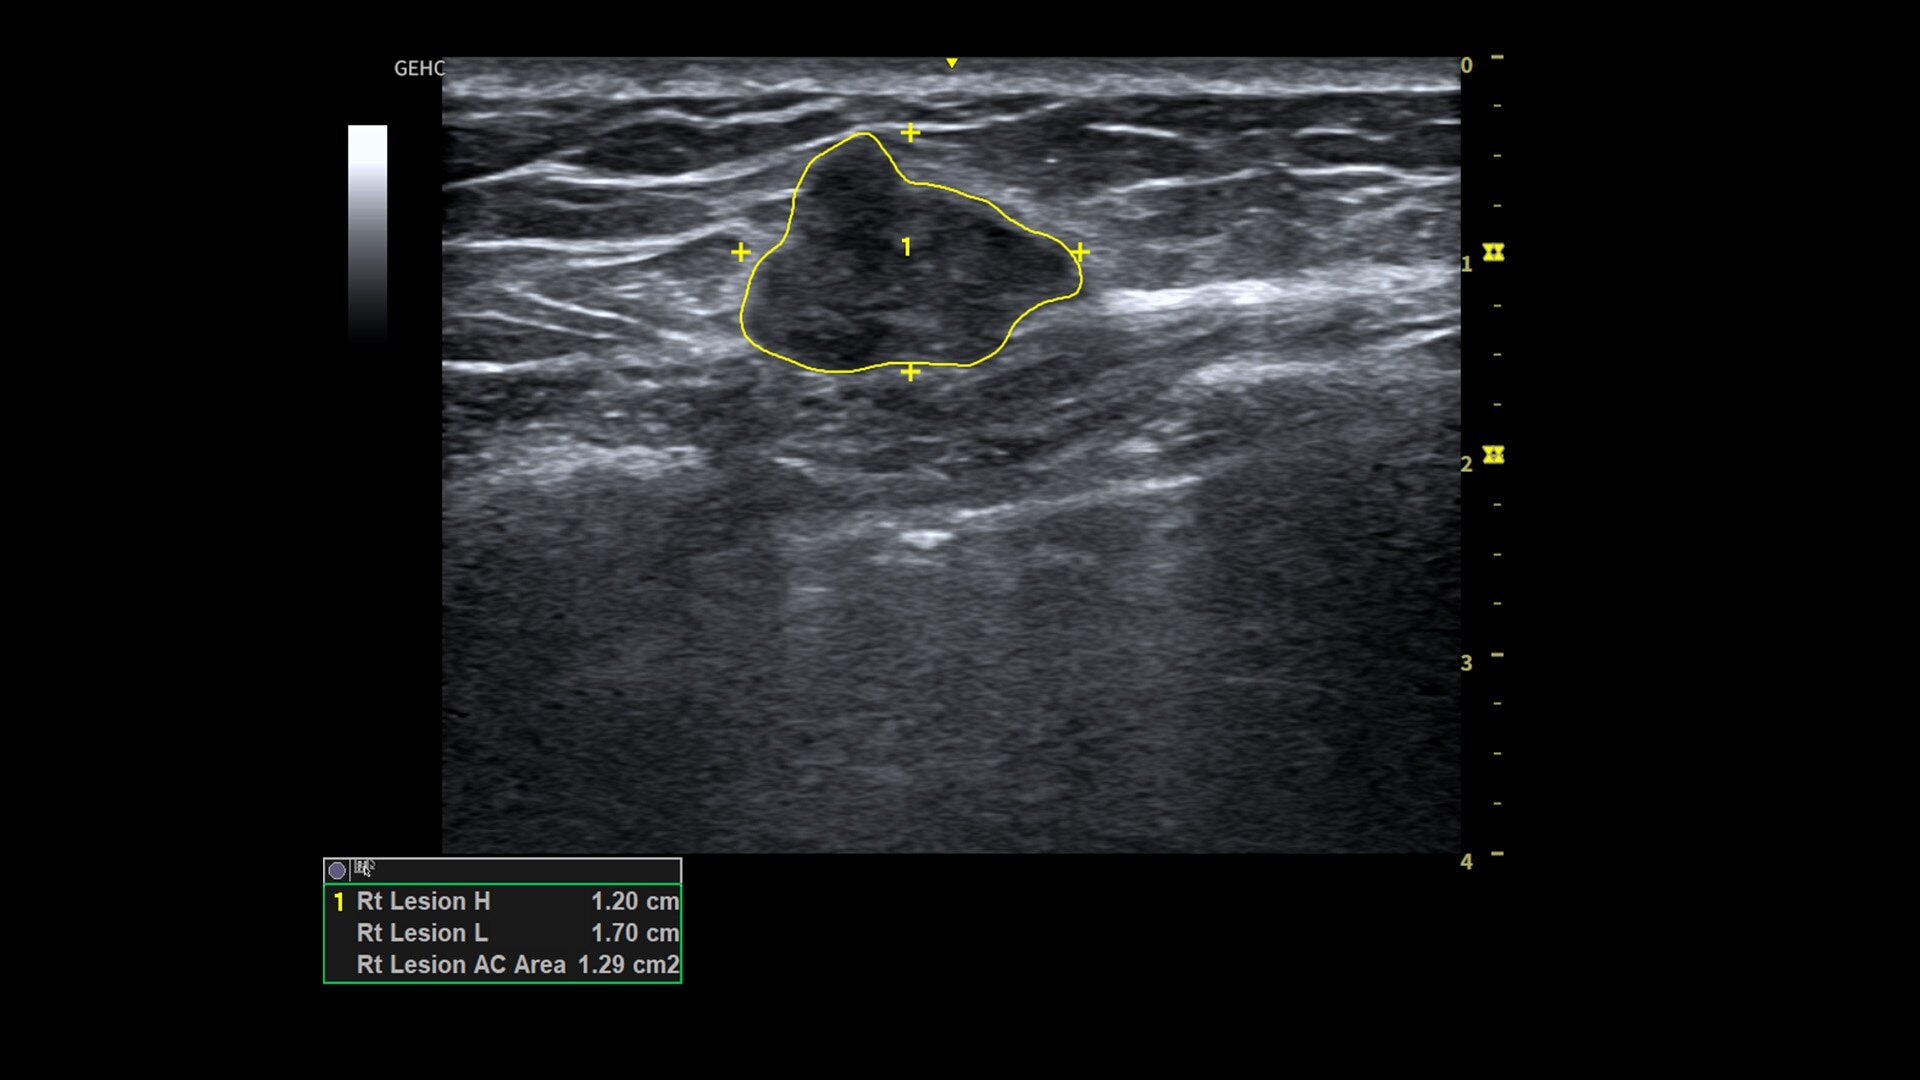

• Make automated 2D Measurements and Volume Calculations with Auto Contour, Auto Bladder, Whizz Follicle and Auto-IMT

• Assess liver, thyroid and breast nodules with Productivity Packages leveraging LI-RADS,® TI-RADS® and BI-RADS® criteria*